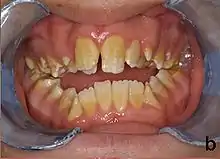

| Amelogenesis imperfecta, hypoplastic type. Note the association of pitted enamel and open bite. | |

People with amelogenesis imperfecta may have teeth with abnormal color: yellow, brown or grey; this disorder can affect any number of teeth of both dentitions. Enamel hypoplasia manifests in a variety of ways depending on the type of AI an individual has (see below), with pitting and plane-form defects common.[4] The teeth have a higher risk for dental cavities and are hypersensitive to temperature changes as well as rapid attrition, excessive calculus deposition, and gingival hyperplasia.[5] The earliest known case of AI is in an extinct hominid species called Paranthropus robustus, with over a third of individuals displaying this condition.[6]